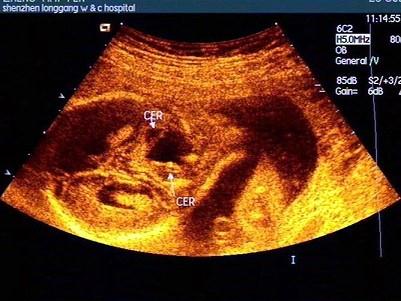

胎儿头颅部超声检查如图,最可能的诊断是?(?)A.正常声像图B.脑积水C.先天性蛛网膜囊肿D.孔洞脑E.小脑蚓部缺损

问题 胎儿头颅部超声检查如图,最可能的诊断是?(?)

选项 A.正常声像图 B.脑积水 C.先天性蛛网膜囊肿 D.孔洞脑 E.小脑蚓部缺损

答案 E